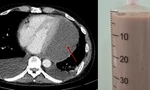

Chỉ trong vòng 30 phút, các bác sĩ đã lấy ra một viên sỏi kích thước lên đến 5x6x6cm – chiếm gần trọn thể tích bàng quang, gây chèn ép nặng nề lên hệ tiết niệu.

| Viên sỏi bàng quang có kích thước lớn như quả trứng gà được các bác sĩ lấy ra khỏi cơ thể người bệnh |